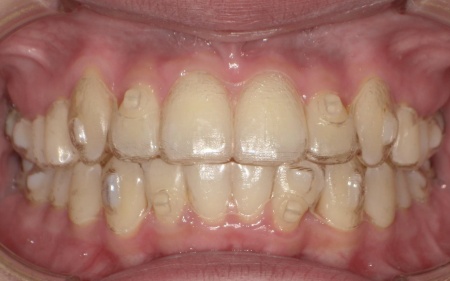

20代女性 八重歯と歯並びの乱れをマウスピース矯正装置で改善した症例

「上下の八重歯が気になる」とご相談いただきました。

拝見したところ、歯が正しく並ぶためのスペースが不足しており、歯が重なって生えてしまう叢生(そうせい)の状態が全体的に見られました。

特に上下の糸切り歯が外側にずれている、いわゆる八重歯が目立っています。